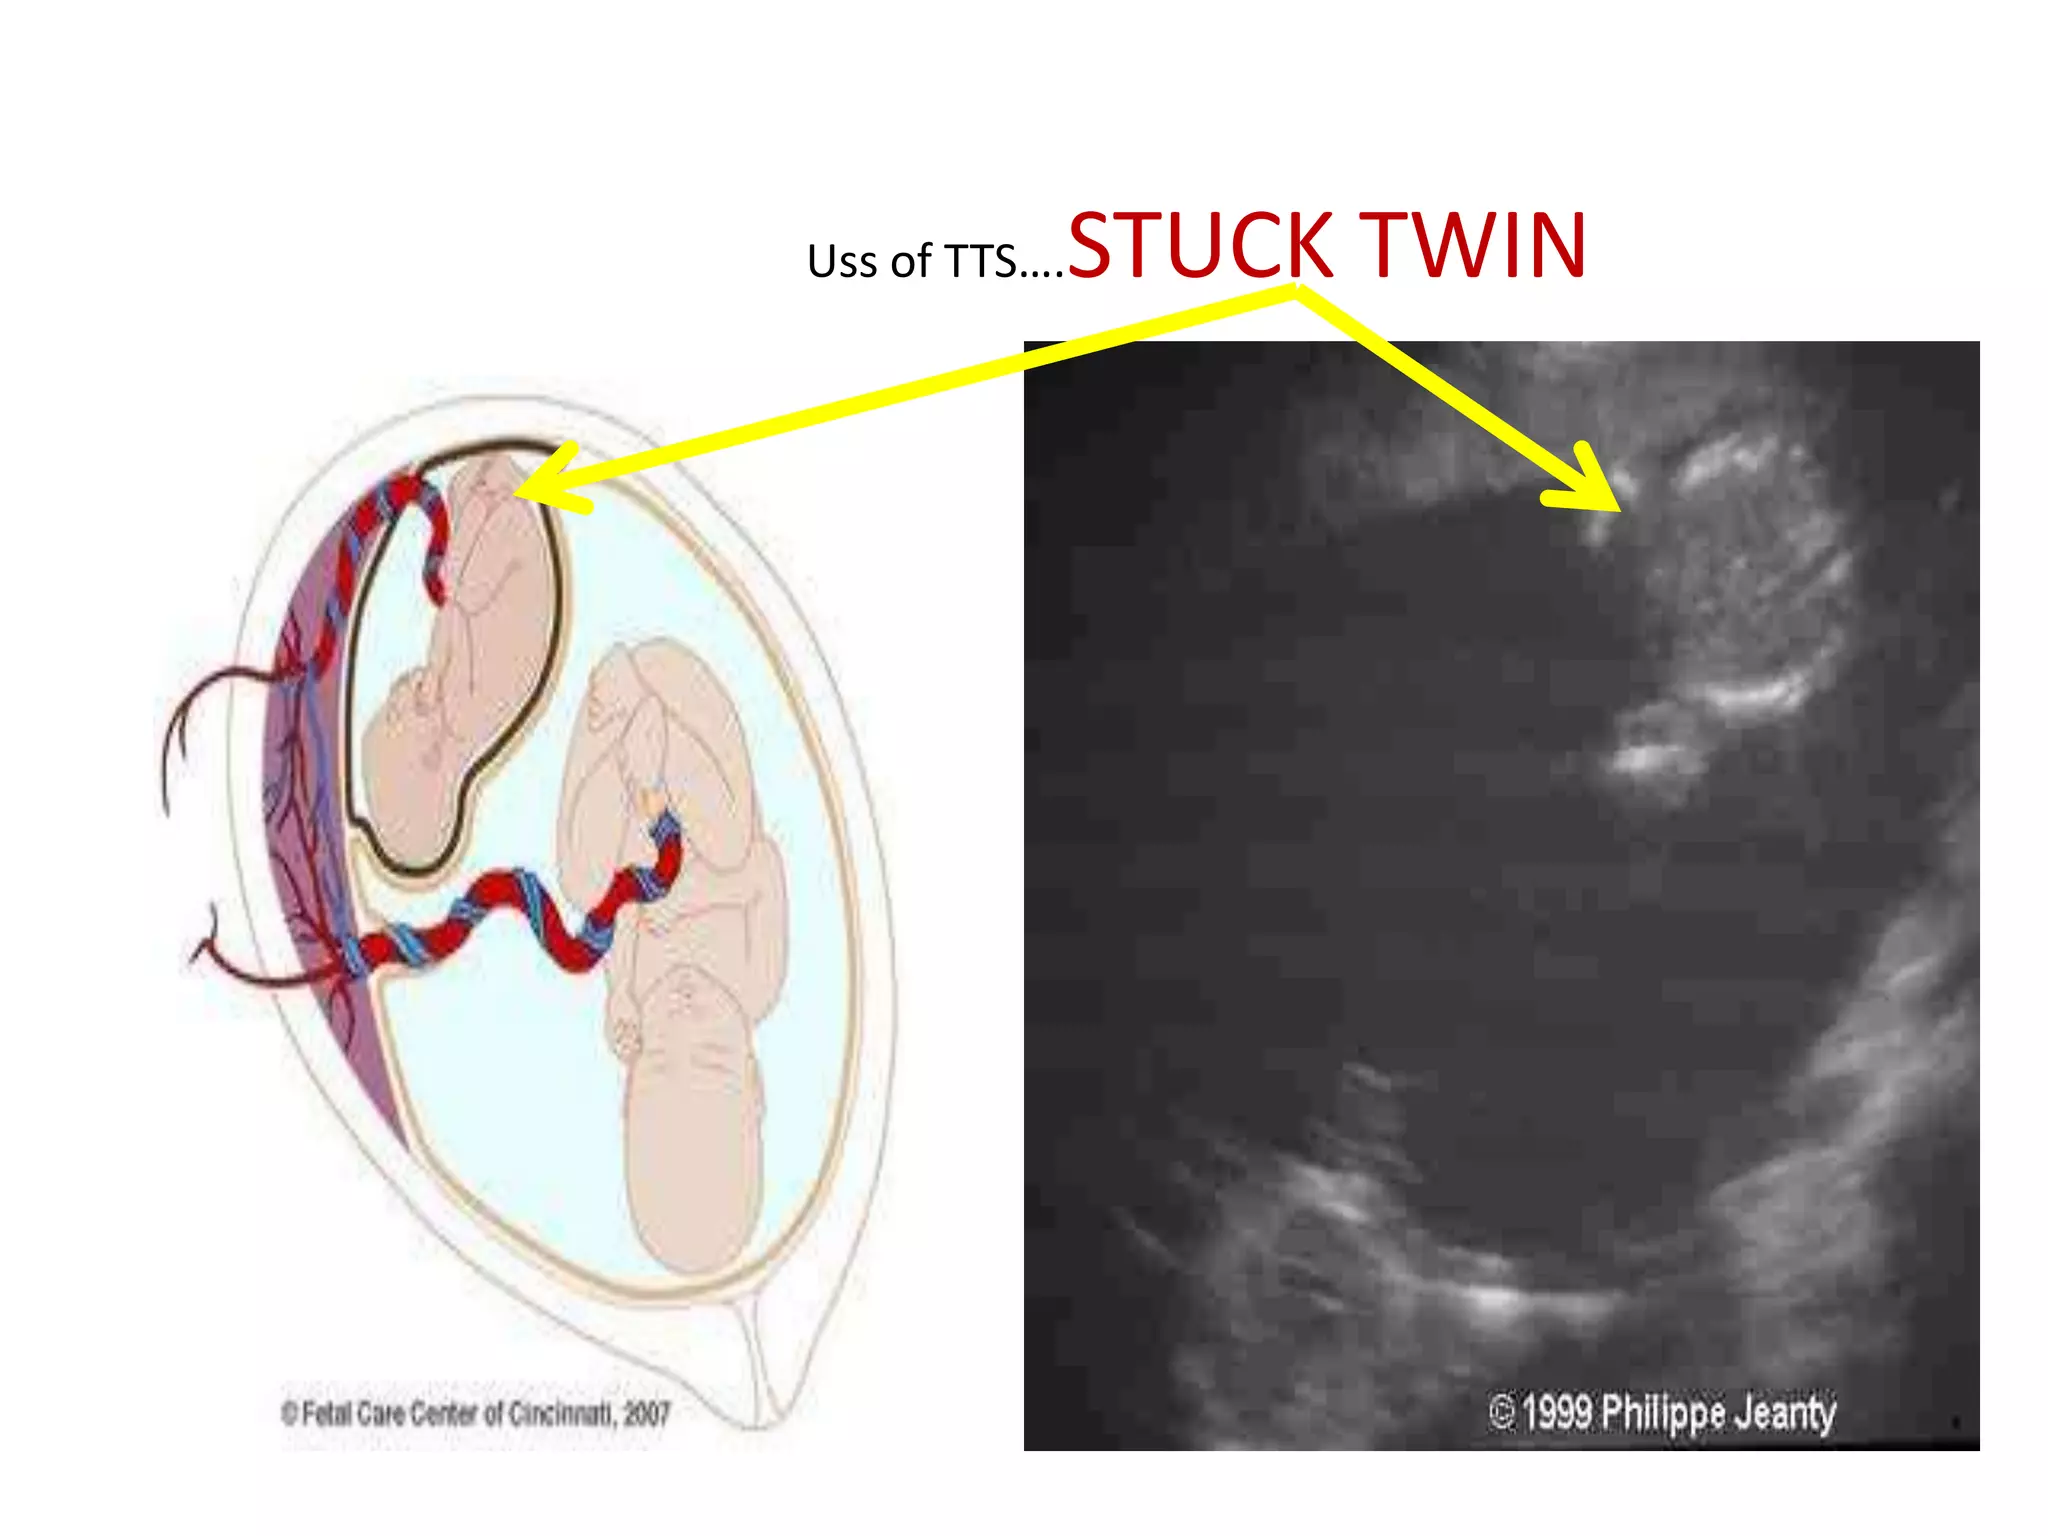

Uss of TTS….   STUCK TWIN